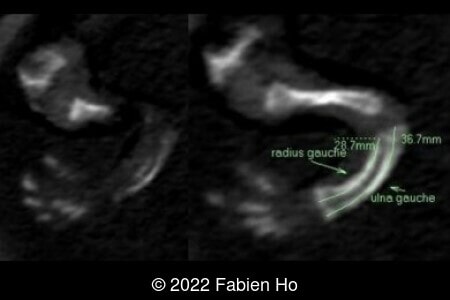

A CT scan was subsequently performed at 32 weeks gestation

The prenatal CT scan showed:

- Very short long bones with curved femurs, tibias and fibulas. The curvature of the long bones reaches a 90° angle concerning for fracture. Upper limbs are moderately curved without fracture.